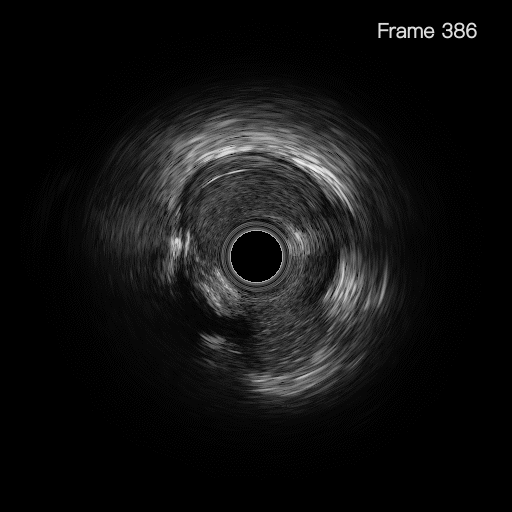

Normal vessel